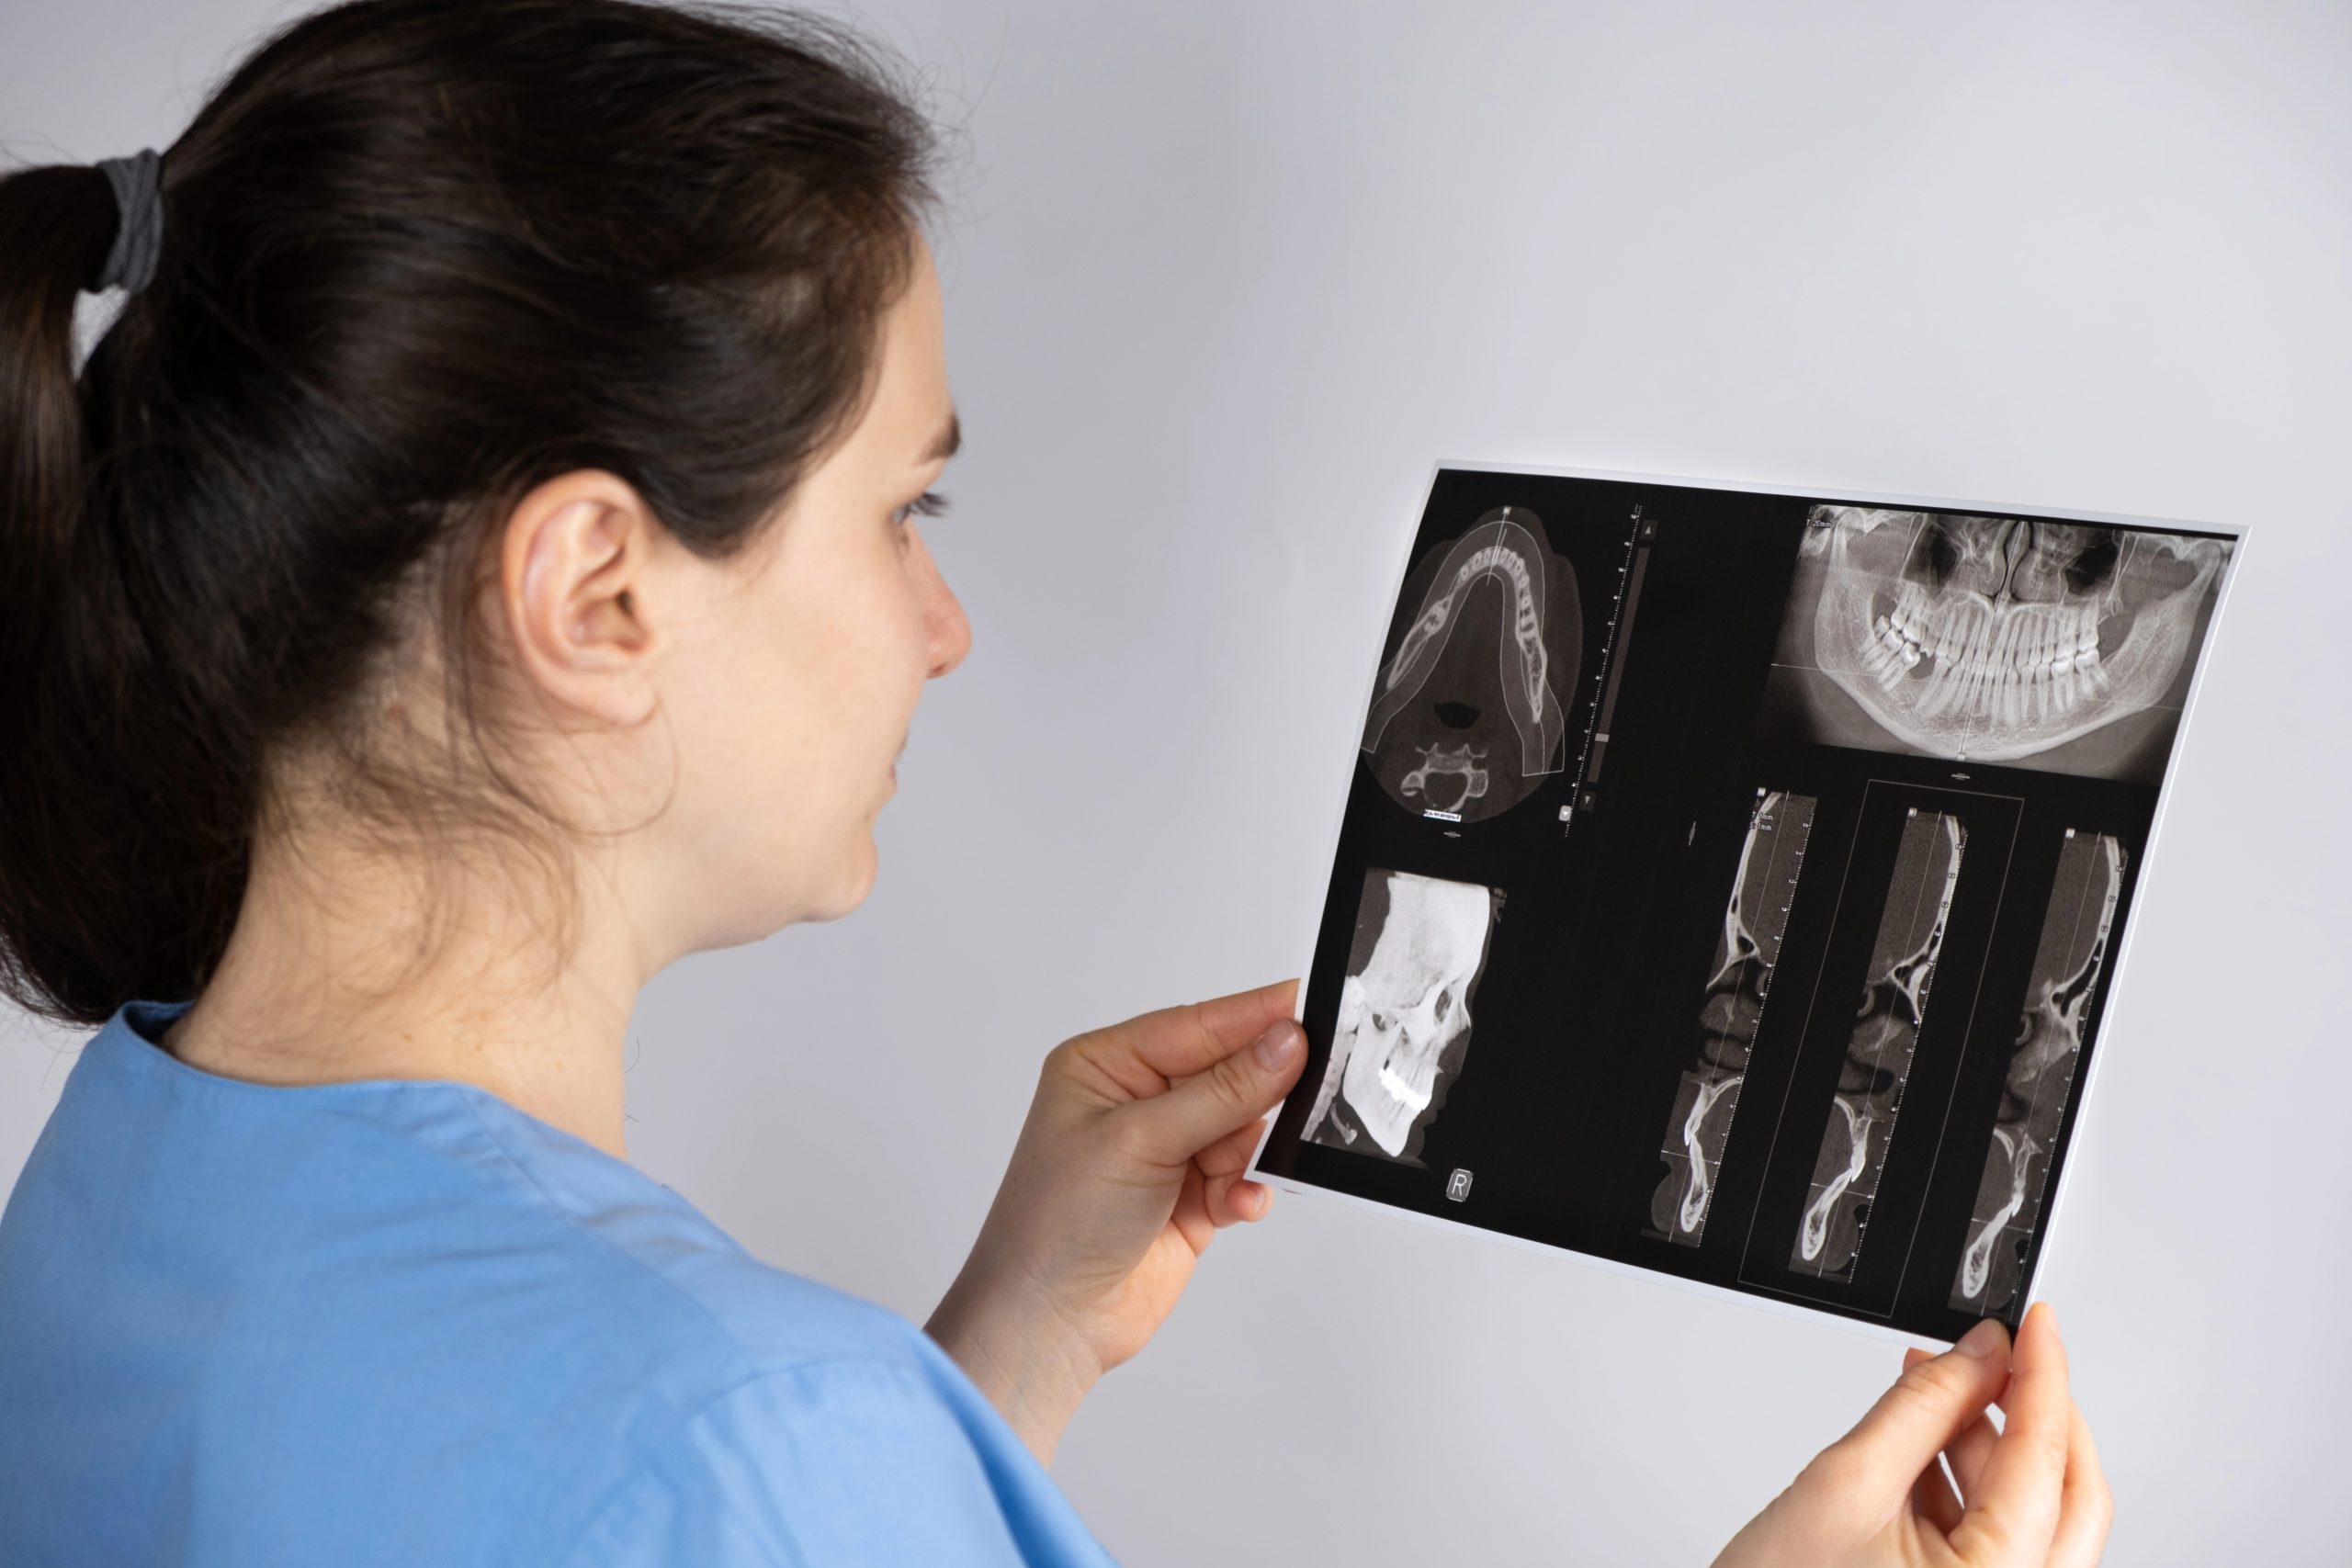

Belterra X-Rays: What Your Dentist Sees in Your Oral Health Screening

If you’ve ever wondered what your dentist is really looking at when viewing your dental X-rays, you’re not alone. At Renken Dentistry Belterra in Austin, we know that being informed about your care helps ease nerves and builds trust. That’s why we take the time to show patients what we’re seeing during their oral health […]